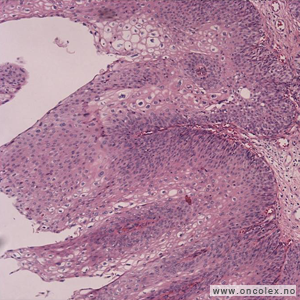

Patologen ser på vevsprøvene under mikroskop for å avgjøre om det foreligger papillom (godartet), karsinom in situ (forstadie) eller karsinom (eventuelt andre ondartede svulster). I tillegg vurderes svulstens malignitetspotensiale og utbredelse. Denne informasjonen er av stor betydning for valg behandlingsmetode og for pasientens leveutsikter. Det kan også være nødvendig med tilleggsanalyser som immunhistokjemi og molekylære analyser for å subklassifisere svulsten.

Svulster i urinveiene klassifiseres i henhold til WHO 2004. Mer enn 99 % av svulstene i urinveiene oppstår i overgangsepitelet (urotelet) som kler slimhinnen i nyrebekken, urinledere, urinblære og øvre del av urinrøret.

Mer enn 95 % av de uroteliale svulstene er ondartede (maligne) og kalles urotelialt karsinom. Ulike varianter av uroteliale karsinomer eksisterer; noen av disse er meget aggressive (mikropapillær type og sarkomatoid).

De høygradig uroteliale karsinomene kan både likne plateepitel (plateepiteldifferensiering) og normale kjertelceller (kjerteldifferensiering). Primære adenokarsinomer i blære forekommer, de er ofte assosiert med intestinal (likner på det en finner i mage-tarmkanalen) metaplasi i urotelet og adenokarsinom in situ. Adenokarsinomer som utgår fra embryonale rester i blæretaket er ofte slimproduserende. Primære plateepitelkarsinomer i blære er sjelden i Norge, og forekommer hos pasienter med kroniske infeksjoner og keratiniserende (forhorning) plateepitelmetaplasi i blæreslimhinnen. I land med endemiske infeksjoner med Bilharzia (Schistosoma hematobium) er platepitelkarsinom i blære mye hyppigere. Småcellet karsinom i blære er meget aggressive svulster; diagnosen bekreftes med immunhistokjemisk undersøkelse. Riktig klassifikasjon av denne svulsttypen er viktig fordi pasientene skal behandles med cellegift primært, og ikke kirurgi.